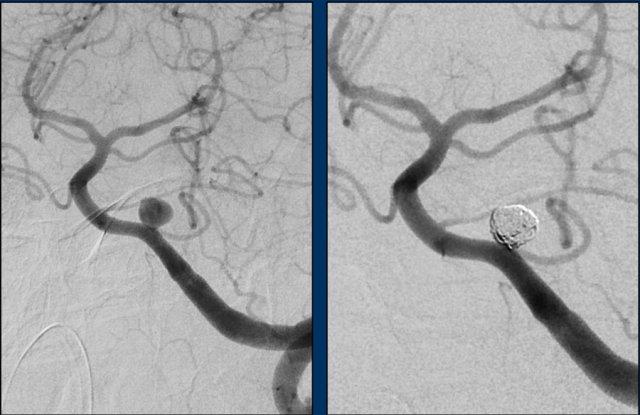

Tiếp tục với DSA…

DSA xác nhận PICA phải kèm túi phình (mũi tên) dẫn đến nidus (vòng tròn).

Nidus được dẫn lưu bởi cả tĩnh mạch nông và tĩnh mạch sâu (không hiển thị riêng biệt ở đây).

Các phát hiện phù hợp với AVM – Spetzler-Martin độ 2:

- Nidus nhỏ (<3 cm): 1 điểm

- Vị trí vùng não không chức năng quan trọng: 0 điểm

- Kiểu dẫn lưu tĩnh mạch bao gồm cả thành phần nông và sâu: 1 điểm

Túi phình hình túi xuất phát từ PICA được giải thích là túi phình liên quan đến dòng chảy.

Do sự thay đổi huyết động học gây ra bởi AVM, thành mạch có thể bị suy yếu và hình thành túi phình.

Các hình ảnh cho thấy DSA trước và sau khi đặt coil túi phình.

PICA, nidus và các tĩnh mạch dẫn lưu bất thường (cùng tạo thành AVM) vẫn còn ngấm thuốc tương phản.

Quyết định không điều trị trực tiếp AVM mà lựa chọn theo dõi và có thể can thiệp phẫu thuật trong tương lai.